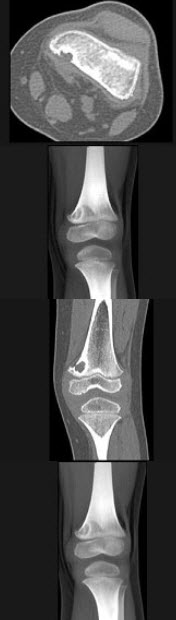

A.软骨下骨组织

左膝关节酸胀不适,摄片发现左胫骨上段局限性骨质改变如图示,最可能的诊断是()

A.非骨化性纤维瘤

B.骨化性纤维瘤

C.内生软骨瘤

D.骨软骨瘤

E.以上均不正确